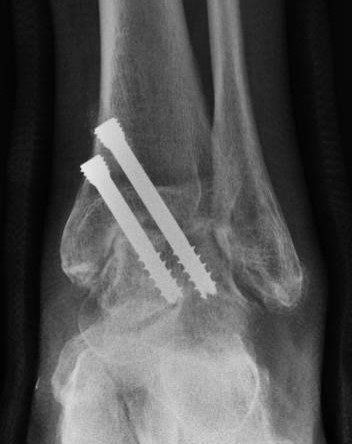

Ankle fusion is permanently stiffening the bones of the ankle together with plates and screws. This procedure is also known ankle arthrodesis.

Dr Beamond performs ankle fusion using three techniques (see images below):

- arthroscopic ankle fusion